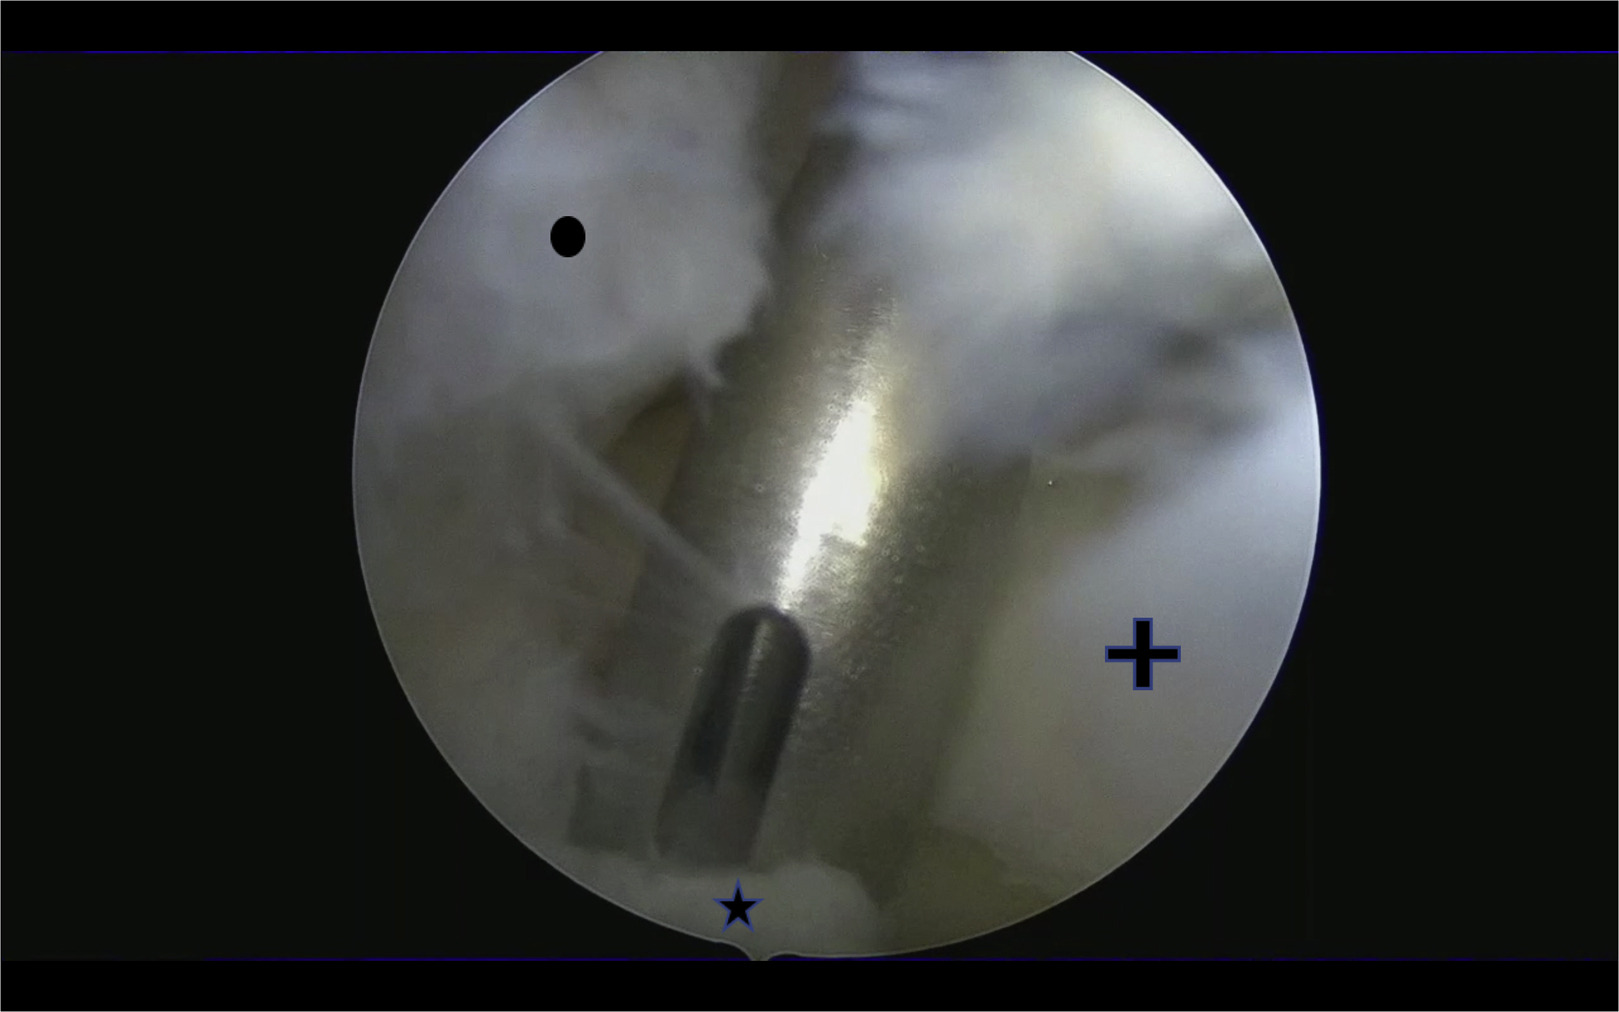

Lateral Meniscus Repair Using Posterolateral Portal: Suture Hook Technique

Lateral meniscus lesions result in loss of meniscus hoop stresses and can lead to lateral compartment overload and early degenerative changes. Arthroscopic suture repair provides good long-term results. However, posterior vertical tears in the peripheral area of the meniscus can be technically challenging to resolve. This Technical Note describes the suture hook technique using an accessory posterolateral portal. We believe it is a safe, effective method for repairing full vertical tears of the lateral meniscus.